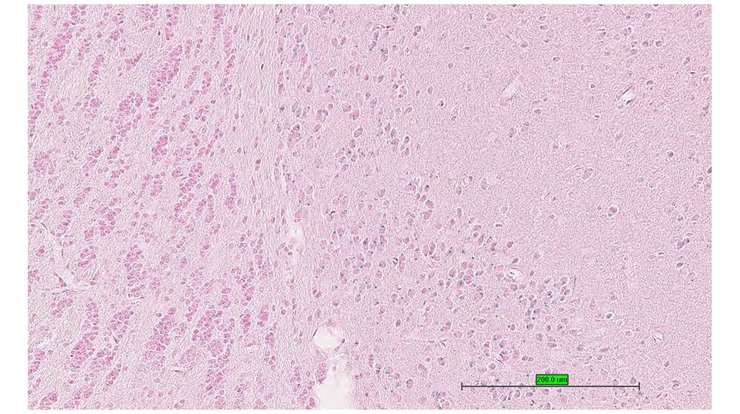

TS28: midbrain Present UC Davis_1877358